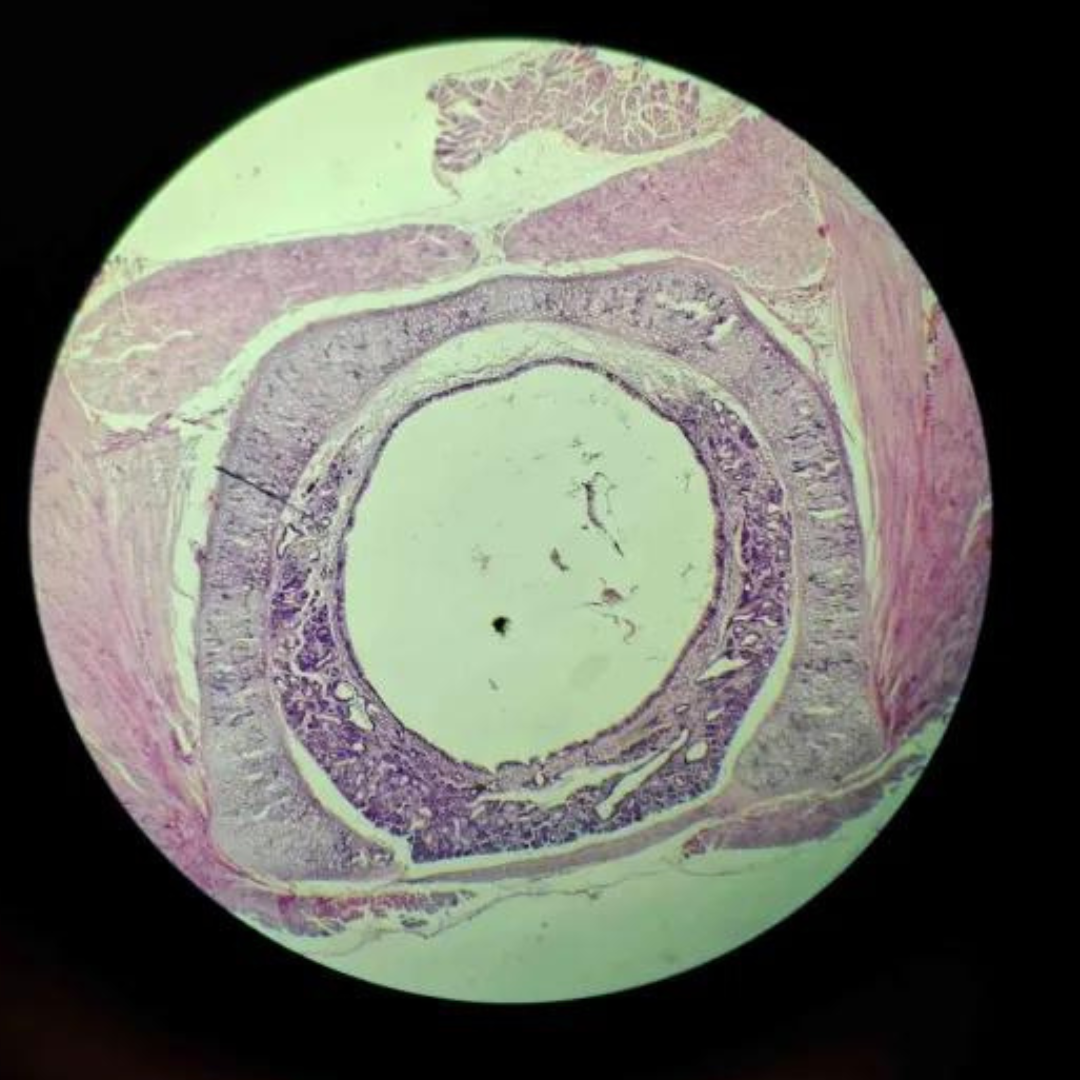

Muscular Arteries (Medium Sized Arteries)

Muscular Arteries (Medium Sized Arteries)

Muscular Arteries (Medium Sized Arteries)

Elastic Arteries (Aorta)

Elastic Arteries (Aorta)

Elastic Arteries (Aorta)